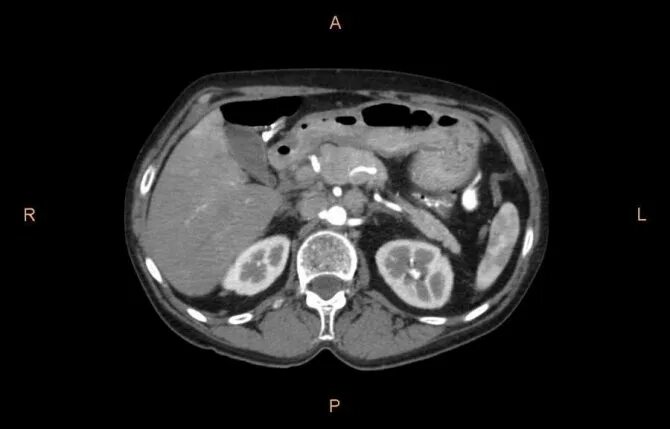

Мрт обп с контрастированием